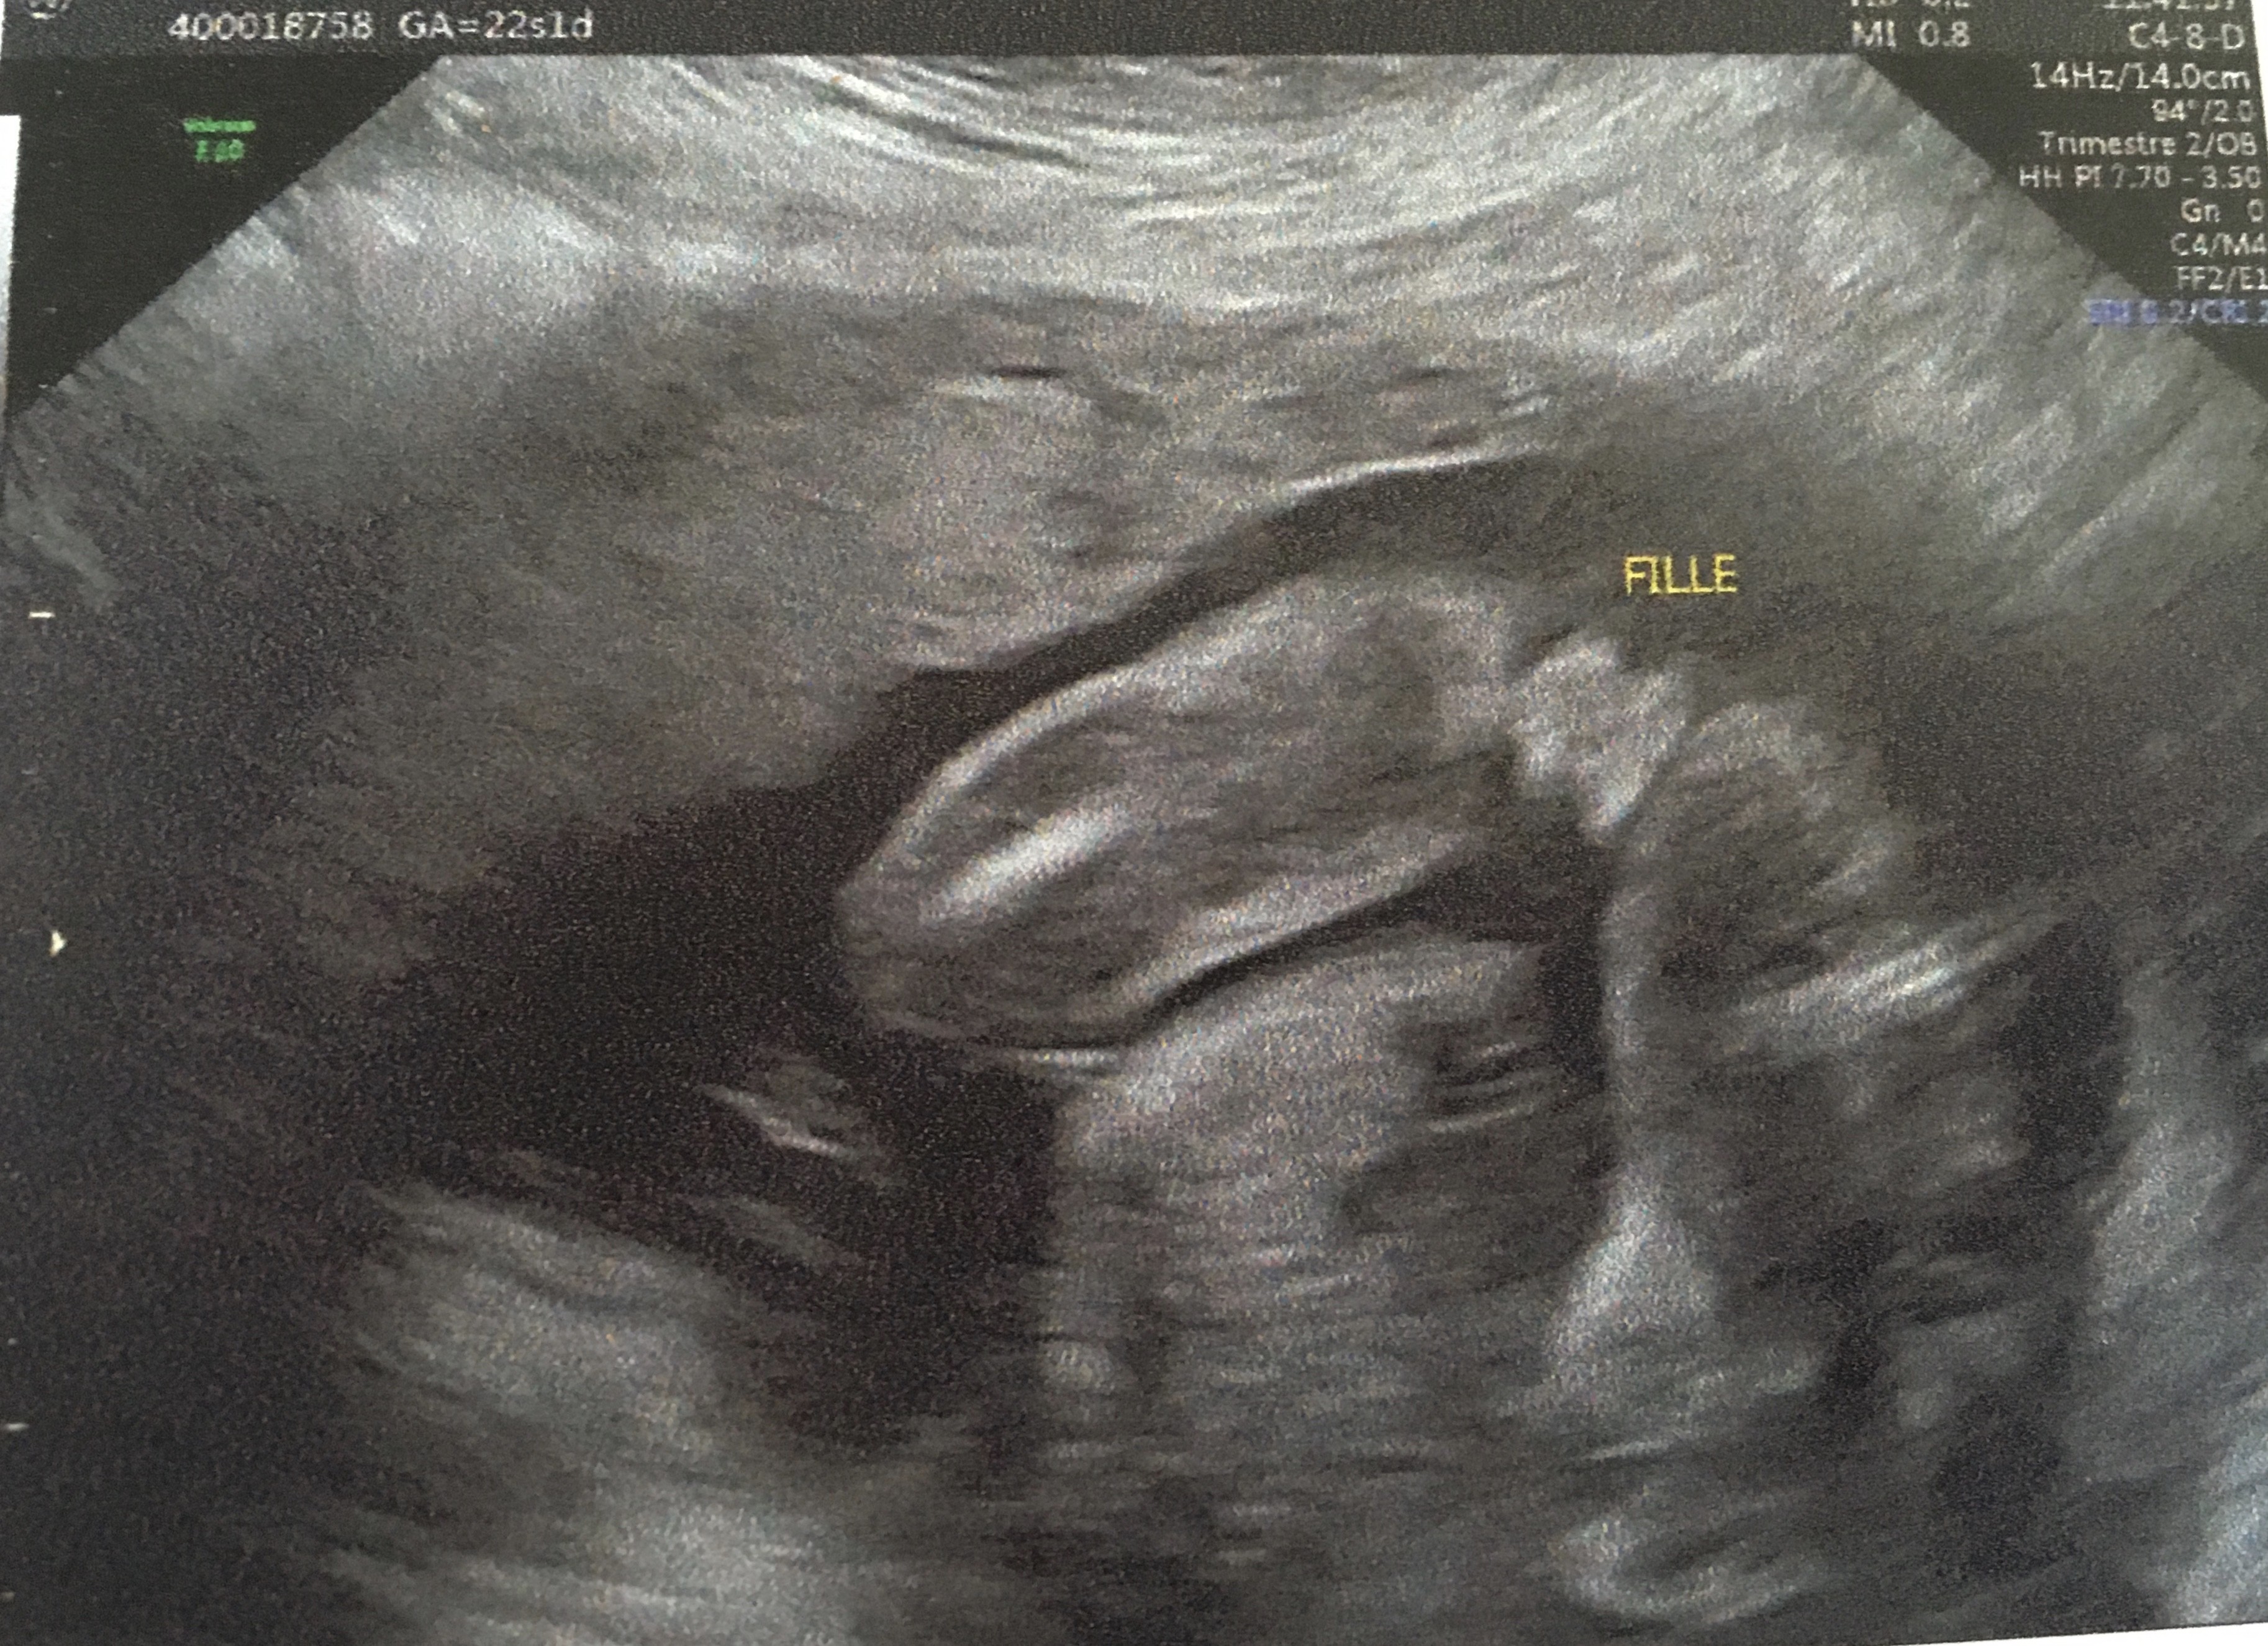

24, une échographie morphologique peut être effectuée Cette analyse offre plus de15 – 16 semaines d'aménorrhée (Je saisGénétiquement dès sa conception, le sexe du bébé

Get premium, high resolution news photos at Getty ImagesL' échographie des 12 semaines Au cours de cet examen, le médecin scrute les différents organes, notamment le tubercule génital Un certain nombre de travaux ont démontréSi le tubercule est perpendiculaire au corps alors c'est probablement un garçon!

Partir du tubercule génital avant 12 SA car le taux d'erreur est de 40 % et donc ne dépasse que de peu l'effet du hasard l'aspect est dit féminin quand le le tubercule génital part vers le bas et horizontalement l'aspect est dit masculin quand le tubercule génital part en avant etFille ou garçon tout se décide lors de la fécondation, au moment même oùDès le début ou plutôt dès la première échographie celle qui se fait vers 12 SA et qui est généralement la première si tu n'as pas eu d'échographie de datation, parce que t'es en impatiente, parce que tu veux commencer à

Le tubercule génital, avant la douzième semaine de grossesse, ne permet pas de déterminer le sexe du fœtus ÀVenir est potentiellement une petite fille Mais, dans certains cas, le bourgeon génital se développe différemment Ainsi, par prudence, la majoritéTubercule fille devient garçon Erreur échographie fille devient garçon à